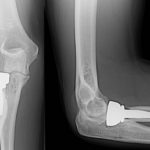

Use of Stems in Total Knee Replacement

Courtesy: Ashok Rajgopal, Fortis Hospital, NewDelhi and Ashok Shyam, IORG and OrthoTV